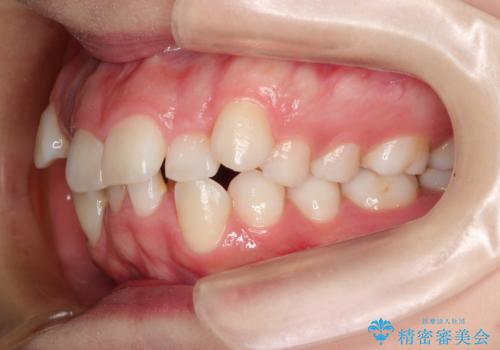

- 前歯のデコボコと上顎の前突感による口の閉じにくさを気にして来院された患者様です。

期間はかかったものの、口元の張り出し感や歯のデコボコが解消され、患者様には大変満足していただけました。